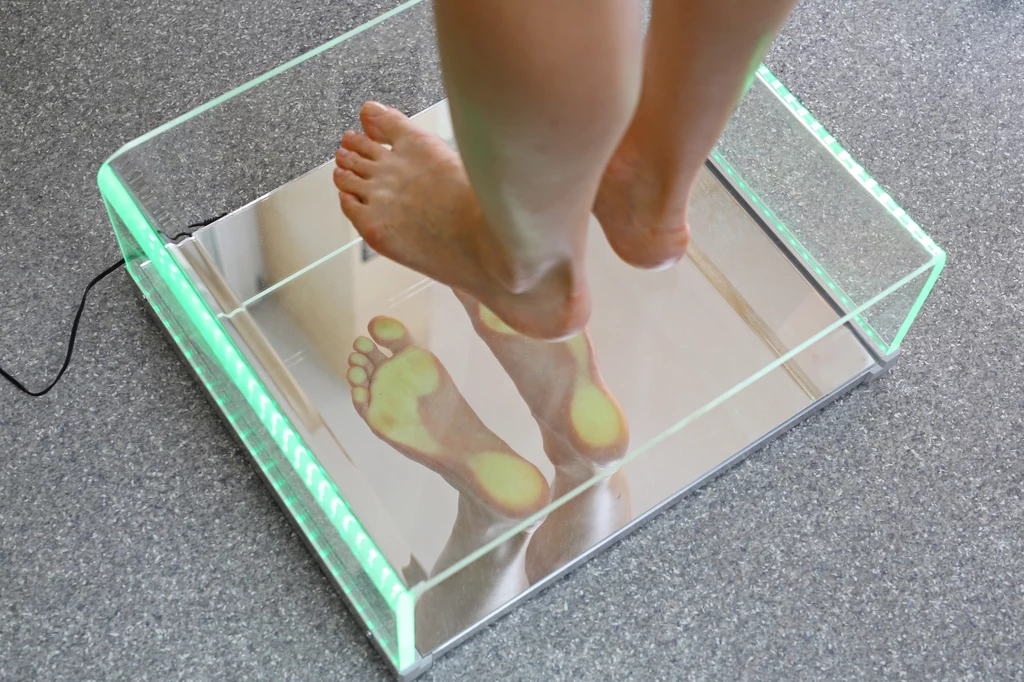

Szybko podejmij walkę z haluksami

Tego nie da się pominąć. Najpierw boli nas kość, potem mamy problemy z chodzeniem w ulubionych szpilkach. Wystarczy spojrzeć… to haluks.

Szybko podejmij walkę z haluksami

Tego nie da się pominąć. Najpierw boli nas kość, potem mamy problemy z chodzeniem w ulubionych szpilkach. Wystarczy spojrzeć… to haluks.